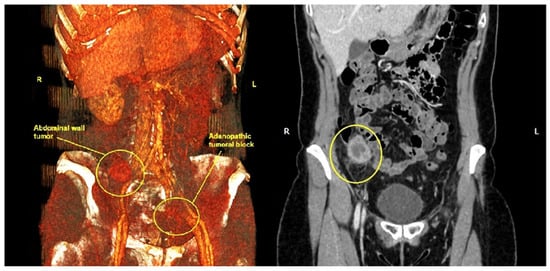

2. Case Description